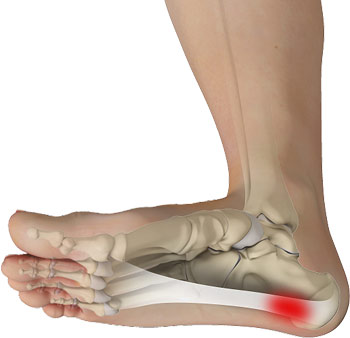

Fasciïtis Plantaris

Irritatie van de peesplaat t.h.v. hielbeen

Onder de voet zit een peesplaat die uitwaaiert richting de bal van de voet. Deze peesplaat heeft een belangrijke functie in het afwikkelen en stabiliseren van de voet bij het lopen. We spreken van fasciïtis plantaris wanneer deze overbelast is geraakt. De overbelasting kan resulteren in een ontsteking en zelfs in een chronische klacht genaamd fasciosis plantaris.

Vooral (start-)pijn aan de onderzijde van de hiel of iets naar voren toe. Vaak is ook een zwelling aanwezig.